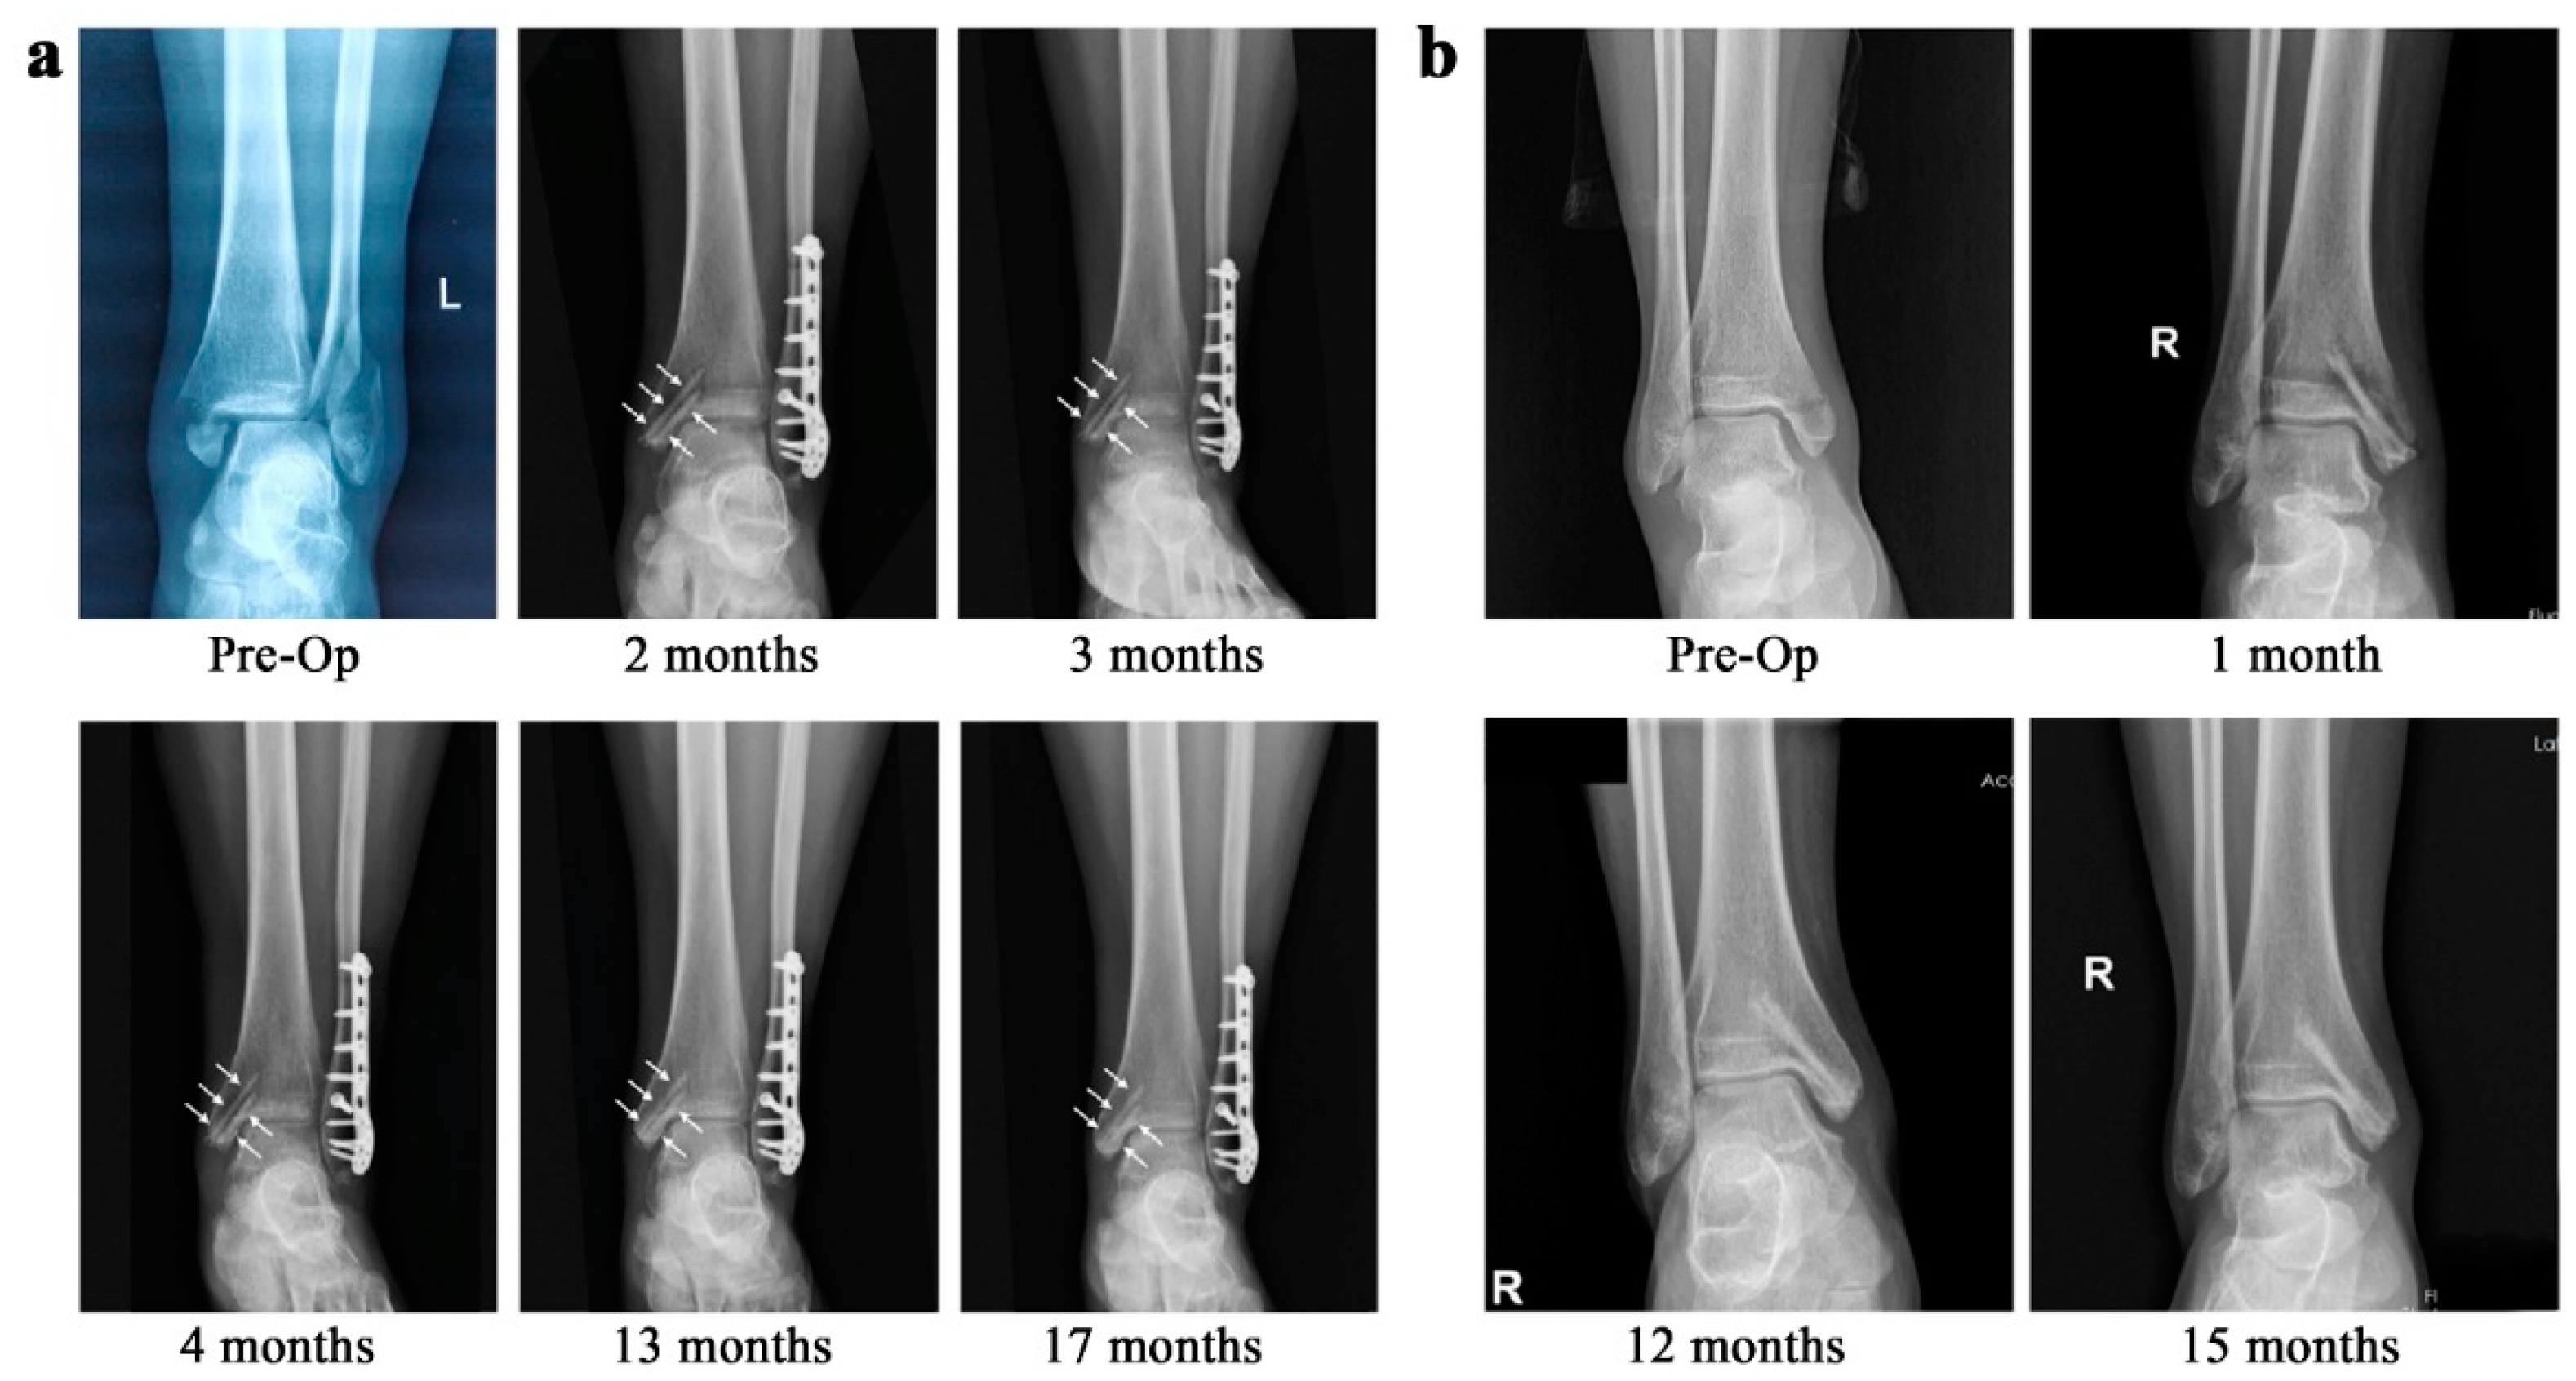

Having the ability to promote in vivo bone healing and regeneration and the mechanical properties similar to that of bones, Mg alloys with suitable coatings have the potential for use as biodegradable orthopedic implants [189,190,191]. These materials coated with calcium phosphate coatings based on hydroxyapatite and its various chemical analogues can further enhance biocompatibility [192], bioactivity [193], wear resistance [194], bone conduction, bone induction, and the degradation resistance of Mg biomaterials [195]. Gao et al. [196] deposited calcium phosphate coating containing dicalcium phosphate dihydrate on an AZ60 alloy via the chemical conversion technique. The in vitro and in vivo results indicated that this coating significantly improved the biocompatibility and biodegradation behavior of the Mg alloy. To provide a solid basis for further clinical translation, the safety and effectiveness of Mg–Nd–Zn–Zr alloy screws coated by Ca–P coating for the treatment of medial malleolar fractures was evaluated [197]. In this study, these modified Mg screws were used to treat nine patients with medial malleolar fractures (Figure 3). Postoperative radiography showed that obvious degradation occurred twelve months postoperatively and all patients achieved good medial malleolar fracture alignment. No one experienced malunion, failure of internal fixation, infection, or breakage of the screws before fracture healing. These results confirm that Ca–P-coated Mg–Nd–Zn–Zr alloy has excellent prospects for clinical translation and can be an alternative internal fixation device for fracture treatment. In a study, Husak et al. [198] applied hydroxyapatite coatings on the surface of Mg alloy with the contents of Mg (96.25 wt.%), Al (1.85 wt.%), Nb (1.25 wt.%), and Zr (0.65 wt.%). The in vitro and in vivo results indicated that the number of adherent cells on the surface of uncoated Mg alloy was significantly less than that on the surface of hydroxyapatite-coated samples, and the degradation rate of this Mg alloy was decreased by hydroxyapatite coating. It is reported that the efficiency of hydroxyapatite-coated Mg alloys can be further improved by using a kind of antimicrobial agent, along with hydroxyapatite [199].

Figure 3.

(a) Preoperative and postoperative radiographs of a young female patient with a trimalleolar fracture. Two Mg–Nd–Zn–Zr alloy screws coated by Ca–P coating (white arrows) were implanted for the treatment of the medial malleolar fracture. Both screws did not indicate signs of failure before fracture healing as they maintained their morphology. The radiographs also indicated the degradation process seventeen months post-surgery. (b) Preoperative and postoperative radiographs of a mid-age female patient with a medial malleolar fracture. The patient’s radiograph indicated radiolucent zones around screws one month postoperatively, which almost disappeared twelve months postoperatively. L and R show Left medial malleolus and Right medial malleolus. Reprinted with permission from Ref. [197]. Copyright 2021, Elsevier.